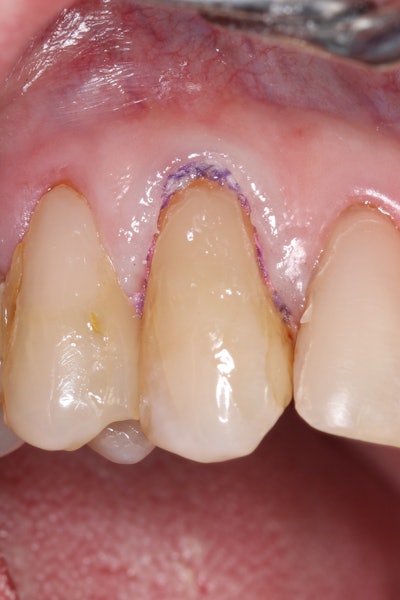

Decay removal was completed with a diamond bur, and the enamel was beveled using a starburst pattern to enhance aesthetic blending (Figure 4). This preparation design was chosen for visual integration rather than bond strength enhancement.

Figure 4: Preparation of the lesion completed with a diamond bur and starburst beveling pattern to enhance aesthetic blending.Figure 4: Preparation of the lesion completed with a diamond bur and starburst beveling pattern to enhance aesthetic blending.